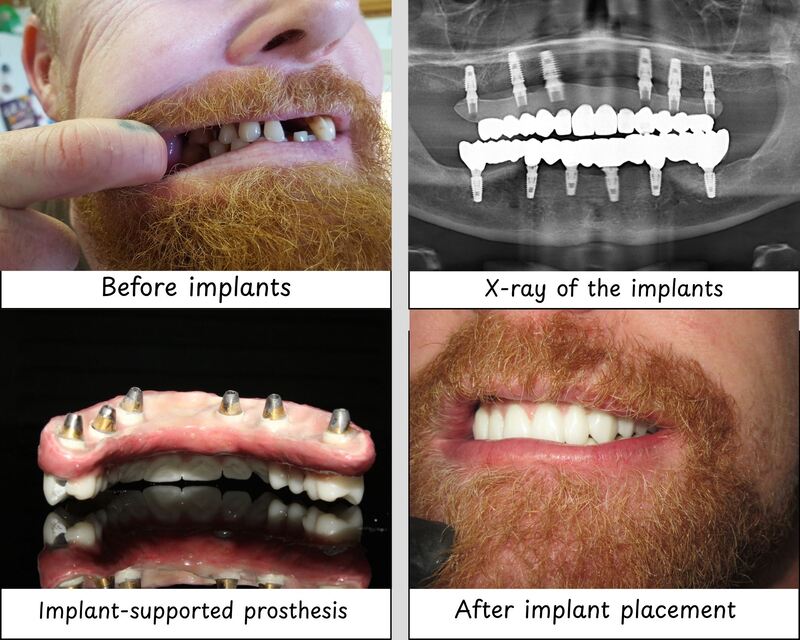

Article Contents Strategic Sourcing: Dental Implants Tijuana Cost Technical Specifications & Standards ROI Analysis & Profitability Importing from China: A Step-by-Step Guide Frequently Asked Questions Strategic Sourcing: Dental Implants Tijuana Cost Professional Dental Equipment Guide 2026: Executive Market Overview Professional Dental Equipment Guide 2026: Executive Market Overview Strategic Insight: The global dental implant market is […]

Article Contents Strategic Sourcing: Dental Implants Mexico Cost Technical Specifications & Standards ROI Analysis & Profitability Importing from China: A Step-by-Step Guide Frequently Asked Questions Strategic Sourcing: Dental Implants Mexico Cost Professional Dental Equipment Guide 2026: Executive Market Overview Dental Implants Mexico Cost Analysis Dental implants represent the cornerstone of modern digital dentistry, enabling precision-driven […]

Article Contents Strategic Sourcing: Dental Implants Las Vegas Prices Technical Specifications & Standards ROI Analysis & Profitability Importing from China: A Step-by-Step Guide Frequently Asked Questions Strategic Sourcing: Dental Implants Las Vegas Prices Dental Equipment Guide 2026: Executive Market Overview Dental Equipment Guide 2026: Executive Market Overview Dental Implants: Las Vegas Market Dynamics & Strategic […]

Article Contents Strategic Sourcing: Dental Implants In Turkey Price Technical Specifications & Standards ROI Analysis & Profitability Importing from China: A Step-by-Step Guide Frequently Asked Questions Strategic Sourcing: Dental Implants In Turkey Price Professional Dental Equipment Guide 2026: Dental Implants in Turkey Market Analysis Professional Dental Equipment Guide 2026: Executive Market Overview Dental Implants in […]

Article Contents Strategic Sourcing: Dental Implants Gps Cost Technical Specifications & Standards ROI Analysis & Profitability Importing from China: A Step-by-Step Guide Frequently Asked Questions Strategic Sourcing: Dental Implants Gps Cost Professional Dental Equipment Guide 2026: Executive Market Overview Professional Dental Equipment Guide 2026: Executive Market Overview Dental Implant GPS Systems: Cost Dynamics in Modern […]

Article Contents Strategic Sourcing: Dental Implants Florida Low Cost Technical Specifications & Standards ROI Analysis & Profitability Importing from China: A Step-by-Step Guide Frequently Asked Questions Strategic Sourcing: Dental Implants Florida Low Cost Professional Dental Equipment Guide 2026: Dental Implants Market Analysis Professional Dental Equipment Guide 2026: Executive Market Overview Dental Implants in Florida – […]

Article Contents Strategic Sourcing: Dental Implants Dallas Cost Technical Specifications & Standards ROI Analysis & Profitability Importing from China: A Step-by-Step Guide Frequently Asked Questions Strategic Sourcing: Dental Implants Dallas Cost Dental Equipment Guide 2026: Executive Market Overview Professional Dental Equipment Guide 2026: Executive Market Overview Dental Implants Cost Analysis & Strategic Procurement in the […]